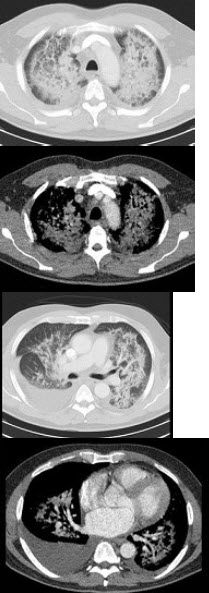

23、单项选择题

女,34岁,新月体肾炎患者,最近咳嗽咯血,第一次行胸片检查考虑为双下肺感染,抗感染治疗后无明显好转,症状加重,4天后复查并行CT检查如图,应考虑为()

A.肺泡蛋白沉着症

B.肺含铁血黄素沉着症

C.双下肺肺炎

D.肺出血肾炎综合征

E.韦格肉芽肿